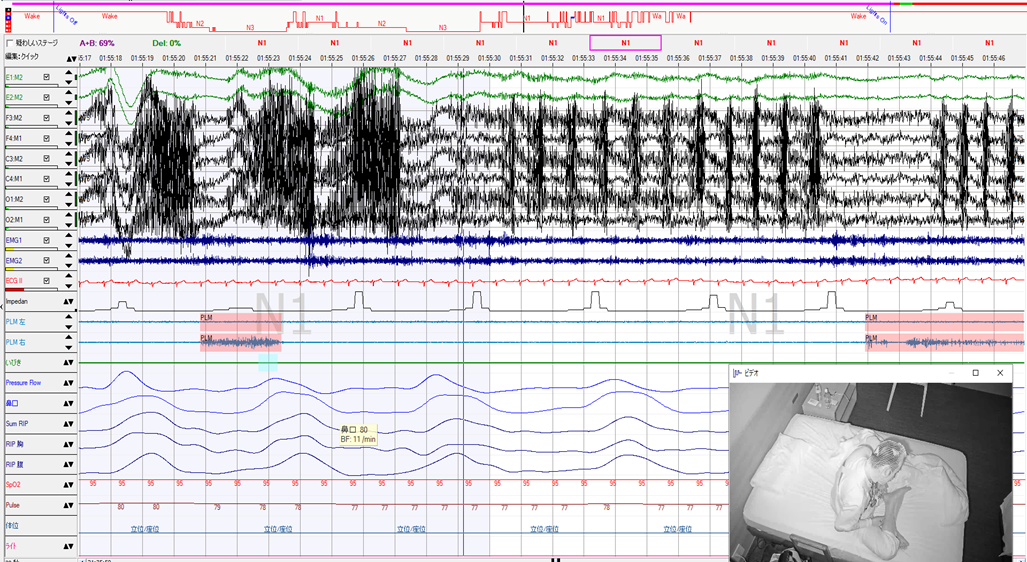

YUMINO'S コラム ゆみのPSGケースカンファ 学会・研究会 主要講演歴 著書出版歴 臨床研究 その他の活動 ゆみのPSGケースカンファ 2026年05月08日 記録前半は閉塞性呼吸イベントが主体で朝方CSR様の周期性呼吸を認めた症例 2026年05月01日 記録前半は閉塞性呼吸イベントが主体で朝方CSR様の周期性呼吸を認めた症例 2026年04月24日 超重症OSA症例の無呼吸と低呼吸 2026年04月14日 やせ型・若年者 でも重症のOSA症例 2026年04月10日 側臥位の就寝時間が長かったにも関わらず、重症の結果だったOSA症例 2026年04月03日 ノンレム睡眠側臥位の安定呼吸時の持続的なSpO2低下 2026年03月27日 CPAPタイトレーションで中枢性無呼吸が残存した症例 2026年03月13日 簡易検査結果と乖離して、大きく軽症化した症例 2026年03月06日 低振幅脳波で入眠判定が困難だったOSA症例 2026年02月27日 側臥位でも呼吸イベントが抑制されない重症OSAと徐波群発 1 2 3 4 5 年別 2026年 2025年 2024年 カテゴリー別